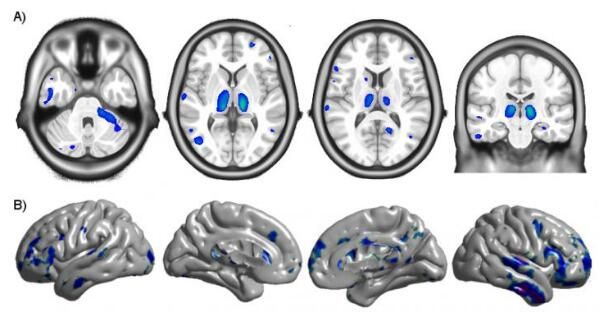

图片来源:Ryan Sanford如今科学家们都知道,HIV的感染会导致大脑某些区域的体积及大脑皮层厚度下降,但研究人员并不清楚这些改变何时会开始,以及组合性抗逆转录病毒疗法(cART,combination antiretroviral therapy)在阻断或减缓这种改变进展上所扮演的关键角色;为了回答这些问题,研究人员通过联合研究,对来自加州大学旧金山分校感染不超过一年的65名HIV感染者进行磁共振成像(MRI)分析。随后研究人员将上述感染者的MRI数据与19名HIV阴性参与者以及感染至少3年的16名HIV阳性患者的相关数据进行对比分析,结果发现,感染后未进行治疗的持续时间越长,个体大脑多个区域的容量就会越小,而且大脑皮层也越来越薄。而一旦cART疗法开始,个体大脑这些区域容量的改变就会停止,而且其大脑中额颞叶区域的皮层厚度也会略微增加。相关研究结果强调了对HIV感染者进行早期诊断的必要性,同时及时进行cART治疗就有可能避免感染者的神经性损伤。HIV的感染会诱发记忆缺失,随后就会诱发个体痴呆症的发生,以及平衡和视觉等问题;早期的筛查和抗逆转录病毒疗法就能有效阻断感染者出现这些症状,同时还能有效阻断未及时治疗的患者机体疾病的进展。研究者Ryan Sanford博士认为,目前从事HIV早期感染中纵向结构神经影像学的研究非常少,而且也并没有任何一项研究在相对较大的样本群体中使用非常敏感性的分析方法;本文研究结果或许就为HIV的早期治疗提供了神经病学领域的研究依据,同时研究人员也希望能利用cART疗法来有效保护HIV感染者大脑免于损伤。最后研究者表示,后期我们还将进行更为深入的研究来寻找诱发HIV感染者大脑损伤的可能性机制,这或为后期科学家们开发新型疗法来逆转感染者大脑的结构性改变提供新的思路和新的线索。原始出处:Sanford R, Ances BM, Meyerhoff DJ, et al. Longitudinal Trajectories of Brain Volume and Cortical Thickness in Treated and Untreated Primary HIV Infection. Clin Infect Dis. 2018 Apr 24. doi:10.1093/cid/ciy362